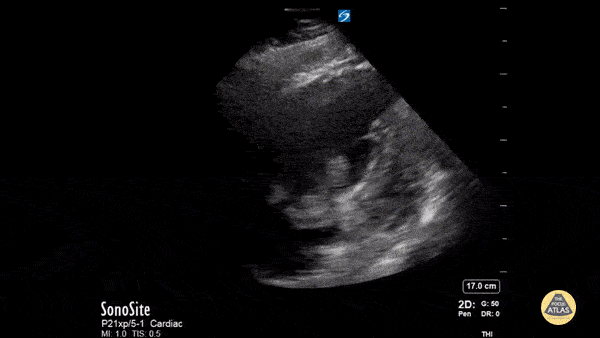

Right Ventricular Dysfunction - McConnell's Sign

This is a middle-aged male who developed dyspnea suddenly while ambulating. Several weeks prior, he had a laparoscopic procedure with a prolonged post-operative course spanning several weeks in the hospital. He denied chest pain or fever. He was tachypneic with otherwise normal vital signs. Lung sounds were clear, although he had obviously increased work of breathing and appeared diaphoretic. Bedside echocardiography revealed a dilated right ventricle with a positive McConnell sign. There was also a large, lobulated, and mobile hyperechoeic mass within the right atrium suspicious for thrombus. CTA of the chest showed bilateral pulmonary emboli. BNP and troponin were moderately elevated, consistent with submassive pulmonary embolism. Andrew Goodrich, MS, DO, PGY-3 Chief Resident, Central Michigan University Emergency Medicine Residency Therese Mead, DO, RDMS, FACEP Associate Program Director and Ultrasound Director, Central Michigan University Emergency Medicine Residency